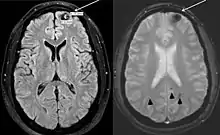

- Lizarraga, Karlo J; De Salles, Antonio AF (20 September 2011). "Multiple cavernous malformations presenting in a patient with Poland syndrome: A case report". Journal of Medical Case Reports. 5 (1): 469. doi:10.1186/1752-1947-5-469. PMC 3195104. PMID 21933407.